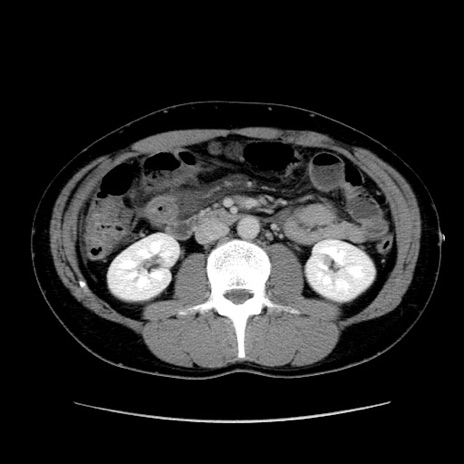

症例36(横断像)

【症例】20歳代 男性

【主訴】心窩部痛

【現病歴】今朝より上腹部痛あり。一旦軽快していたが再度出現したため救急要請。昨日夕に白身の魚を含む刺身を食べた。

【身体所見】BP 136/89mmHg、HR 74/min、BT 37.0℃、腹部:膨満、軟、心窩部に圧痛あり。反跳痛なし、筋性防御なし、腸雑音やや亢進あり。

【データ】WBC 17700、CRP 0.48